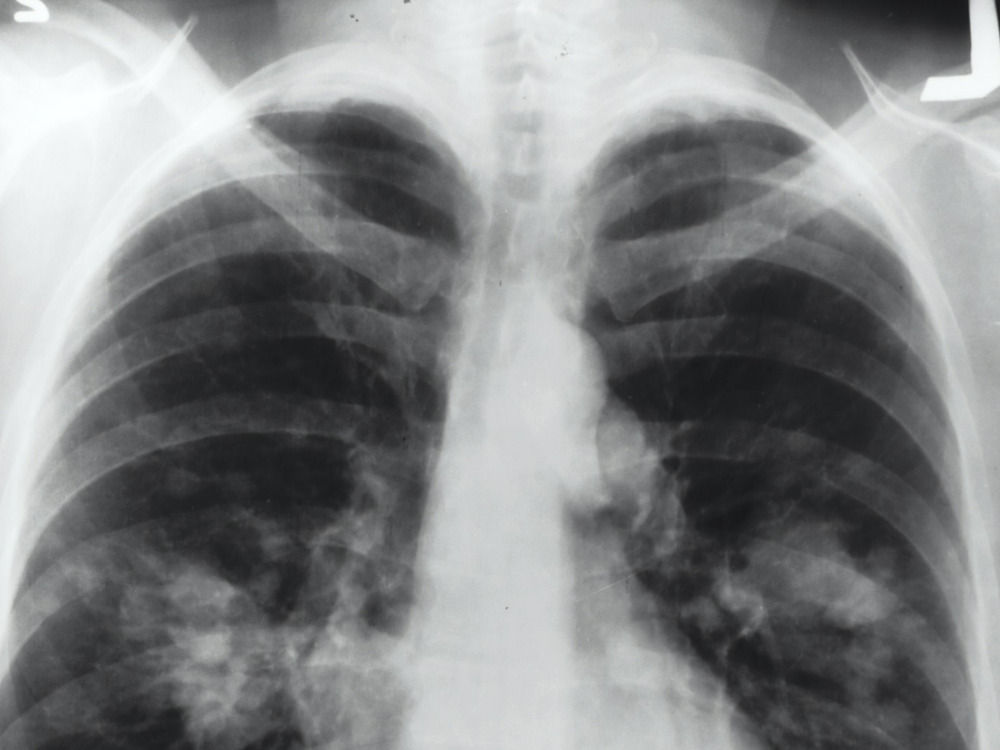

Photo for representational purposes only